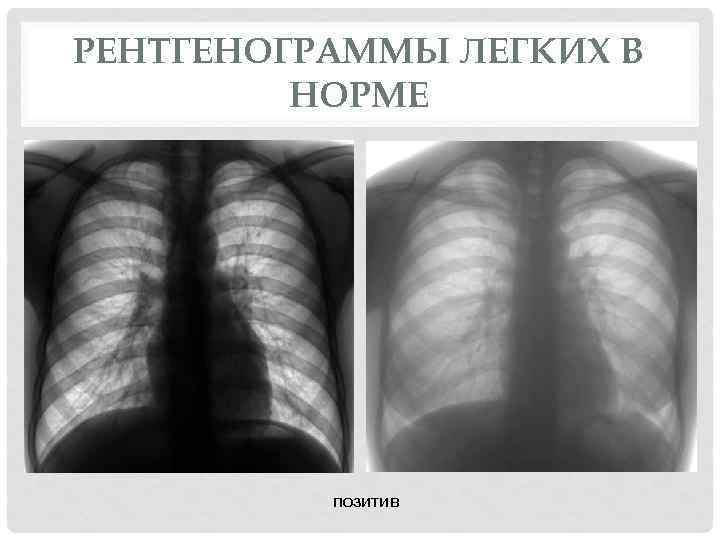

Нормальная рентгенограмма легких: что нужно знать

Раздел: Мудрость в объективе